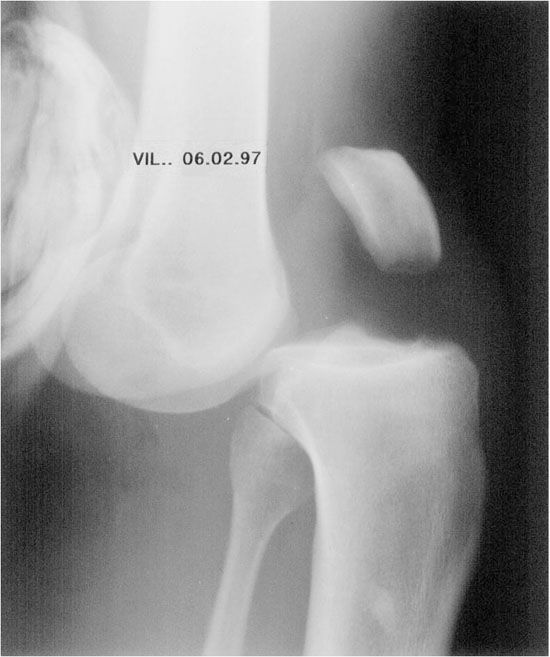

Mise au point Stratégie diagnostique dans les pentades et les luxations du genou , Dominique Saragaglia Service de Chirurgie Orthopédique et de Traumatologie du Sport C.H.U. de Grenoble - Hôpital Sud, Grenoble, France , C. Chaussard Service de Chirurgie Orthopédique et de Traumatologie du Sport CHU de Grenoble, Hôpital Sud 38130 Echirolles N°143 - Avril 2005 ● 23 min de lecture